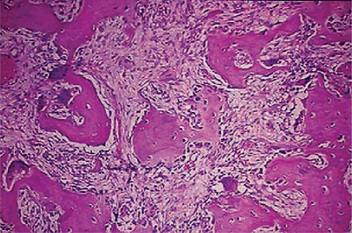

The microscopic appearance of the bone in cases of osteitis deformans varies remarkably, depending upon the stage of the disease encountered. The initial osteolytic phase is marked by disordered areas of resorption by an increased number of overtly large osteoclasts. These abnormal osteoclasts may contain as many as 100 nuclei. The subsequent osteoblastic phase follows with haphazard laying of new bone matrix and formation of woven bone without regard to the patterns of stress. Repeated episodes of bone removal and formation results in the appearance of many small irregularly shaped bone fragments that appear to be joined in a jigsaw or mosaic pattern with deeply staining hematoxyphilic reversal lines (Fig. 17-32). This pattern is the histologic hallmark of Paget’s disease. As the disease progresses, the osteoblastic phase predominates, and excessive abnormal bone formation occurs, causing more compact and dense bone. The pagetic bone is coarse and fibrous, with an avidity for calcium and phosphorus. Marrow spaces are filled with loose highly vascularized connective tissue. The hypervascular bone combined with cutaneous vasodilation causes an increase in the regional blood flow and accounts for the rise in skin temperature seen clinically. The hypervascularity consists of an increased number of patent capillaries and dilated arterioles, as well as of larger venous sinuses (Fig. 17-33).

Figure 17-32 Osteitis deformans.

Photomicrographs of bone in different stages showing (A) reactive phase, (B) mosaic pattern, and (C) resting phase. Note the prominent resting and reversal lines in B.

Figure 17-33 This photomicrograph taken from a bone biopsy from a patient with Paget’s disease of bone shows several bone spicules in a highly vascularized connective tissue stroma.

These areas of bone formation alternate with areas of bone resorption characterized by the presence of osteoclasts. Typically, the osteoclasts are seen inside of Howship lacunae.